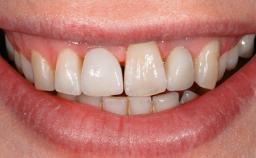

A 77-year-old male patient was referred for the management of frequent and repeated acrylic fracture of his existing mandibular fixed full-arch implant-supported metal/acrylic prosthesis. He also complained about softtissue soreness and the lack of retention and stability of his maxillary removable partial metal/acrylic prosthesis. Both prostheses had been delivered two years previously as part of his full-mouth rehabilitation (caries, tooth wear, tooth fracture). His medical history revealed high blood pressure, controlled with the use of antihypertensive medication.

Patient's Esthetic Expectations Low Medium High

Lip Line No exposure of papillae Exposure of papillae Full exposure of mucosa margin